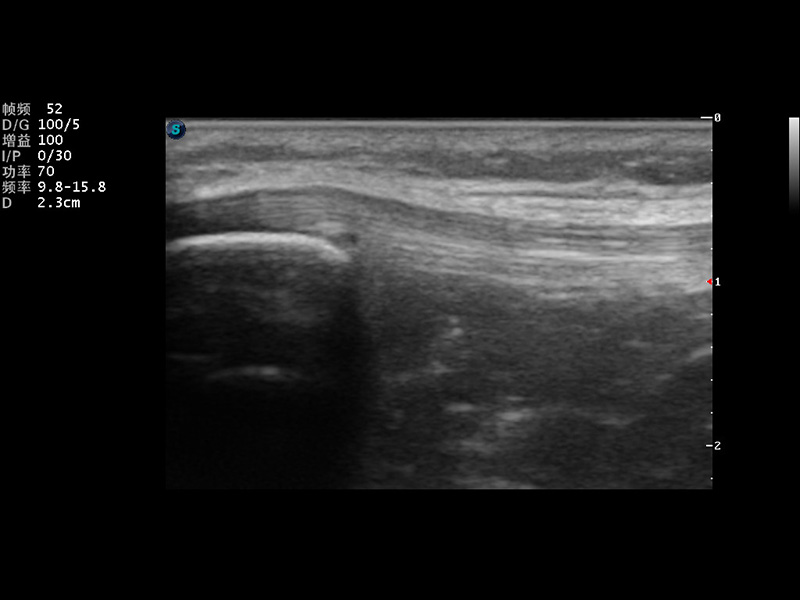

μ-Scan微米成像

实时宽景成像